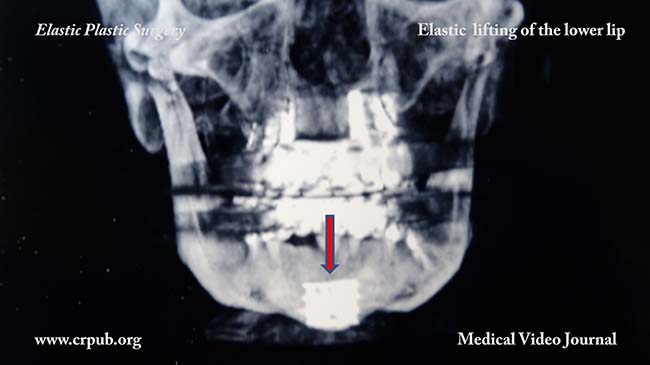

59. Elastic lifting of the lower lip This patient asked us to correct the detachment and drooping of her lower lip, the outcome of maxillofacial surgery performed years earlier to reduce the length of her face. During the maxillofacial operation, her chin was reduced and reinforced with a metallic plate, which caused the tissues of the chin to lose their adherence. This loss of adherence caused the lip to sag and droop. This can easily be corrected by implanting an elastic thread (Elasticum EP4), to suspend the lower lip to the two fasciae of Loré. Elastic lifting of the lower lip can also be carried out to reduce the visibility of the lower teeth. As is known, the elastic thread is impalpable and, once colonised by connective cells, is transformed into a natural "ligament". |